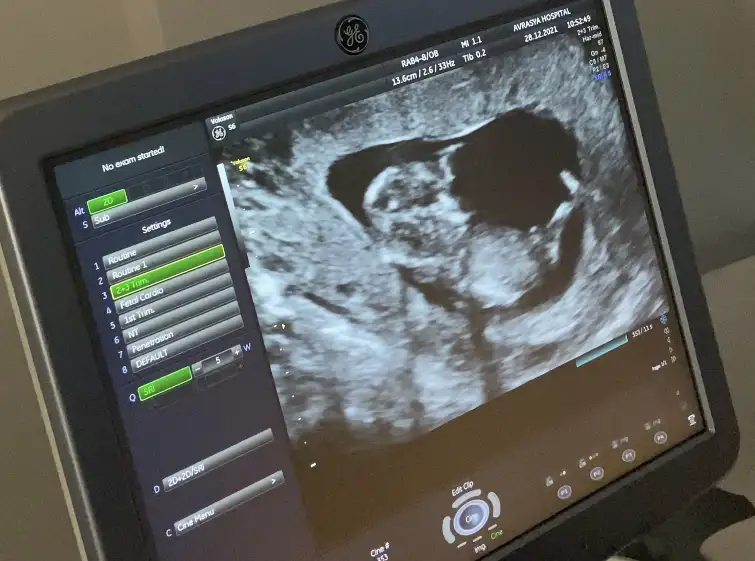

Erkek gibi sanki12+1 fikri olan var mı?

Erkek gibi nubu dik görünüyor12 haftalik usg yorum yaparmisiniz rica etsem